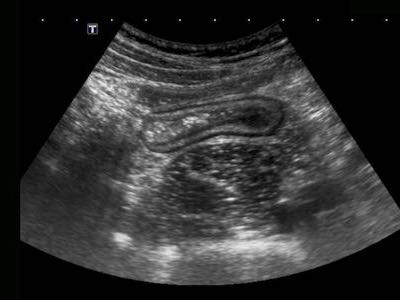

Bệnh nhân nam 18 tuổi này nhập viện với các triệu chứng giống viêm ruột thừa cấp và được chụp CT ngay lập tức.

CT cho thấy hình ảnh dày thành hồi tràng rõ rệt và ruột thừa bình thường (không hiển thị ở đây).

Siêu âm tiếp theo cho thấy các thay đổi giảm âm xuyên thành đặc trưng điển hình trong lớp dưới niêm mạc tăng âm, xác nhận chẩn đoán viêm hồi tràng do Crohn.

Lưu ý độ phân giải hình ảnh vượt trội của siêu âm so với CT.

Ở những bệnh nhân có bệnh Crohn hoạt động rõ ràng, cấu trúc siêu âm bình thường của thành ruột có thể bị mất lan tỏa.

Lưu ý mô mỡ tăng âm (fat) xung quanh hồi tràng, đại diện cho mạc treo và mạc nối đang viêm, đang cố gắng bao bọc lại vị trí thủng sắp xảy ra.

Trong những trường hợp như thế này, hình thái thay đổi và lòng ruột hẹp lại có thể bắt chước hình ảnh ác tính.